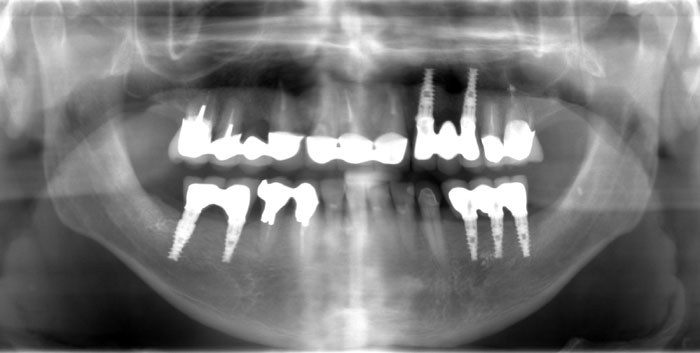

Es ist z. B. möglich, eine Brücke für drei Zähne auf zwei Implantaten aufzubauen, oder eine Brücke für zwölf Zähne von acht Implantaten tragen zu lassen.

Unter Umständen sind auch Mischlösungen möglich, wenn eine Brücke gleichzeitig von Implantaten und von natürlichen Zähnen getragen wird.

Fall Nr. 1: Brücke auf Alpha-Bio-Implantaten und Brücke auf natürlichen Zähnen

Fall Nr. 2: Mischbrücke auf Alpha-Bio-Implantaten und natürlichen Zähnen

Fall Nr. 3: Brücke auf Alpha-Bio-Implantaten und Brücke auf natürlichen Zähnen